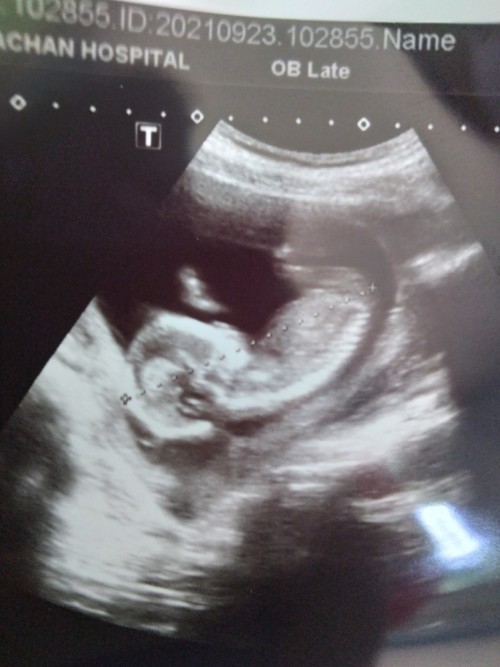

ซาวตอน14wค่ะ ตอนนี้19wแล้ว ทีมมีนาค่ะ🥰

14w 3d นัดผ่าคลอด 21 มีนา 65 ยังไม่รู้เพศเลย ... 😘